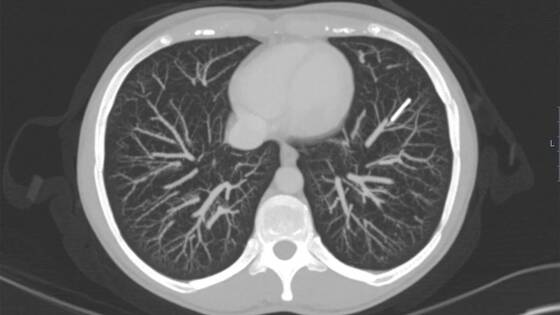

Когда женщина вспомнила про инородное тело в организме, она решила его удалить. Она обратилась к врачам, однако те не смогли обнаружить имплант в положенном месте. В попытках его найти специалисты сначала сделали пациентке рентгенографию, а затем — КТ с контрастом. В итоге имплантат удалось обнаружить в одной из артерий левого легкого, куда он мигрировал по венозному пути через сердце. При этом никаких признаков воспаления в легком, кашля, одышки, боли в груди или кровохаркания у женщины все эти годы не было.

Отмечается, что, если бы она обратилась за медицинской помощью, как только заметила, что не может нащупать контрацептив, его можно было бы извлечь малоинвазивным способом. Однако за шесть лет он врос в легкое, поэтому извлечь его можно было, лишь удалив два сегмента нижней доли органа. Узнав о возможных рисках и осложнениях после операции, женщина от нее отказалась. Поскольку жалоб на здоровье у нее не было, врачи согласились с ее решением, но посоветовали при появлении боли в груди или кашля с кровью незамедлительно обратиться в больницу.